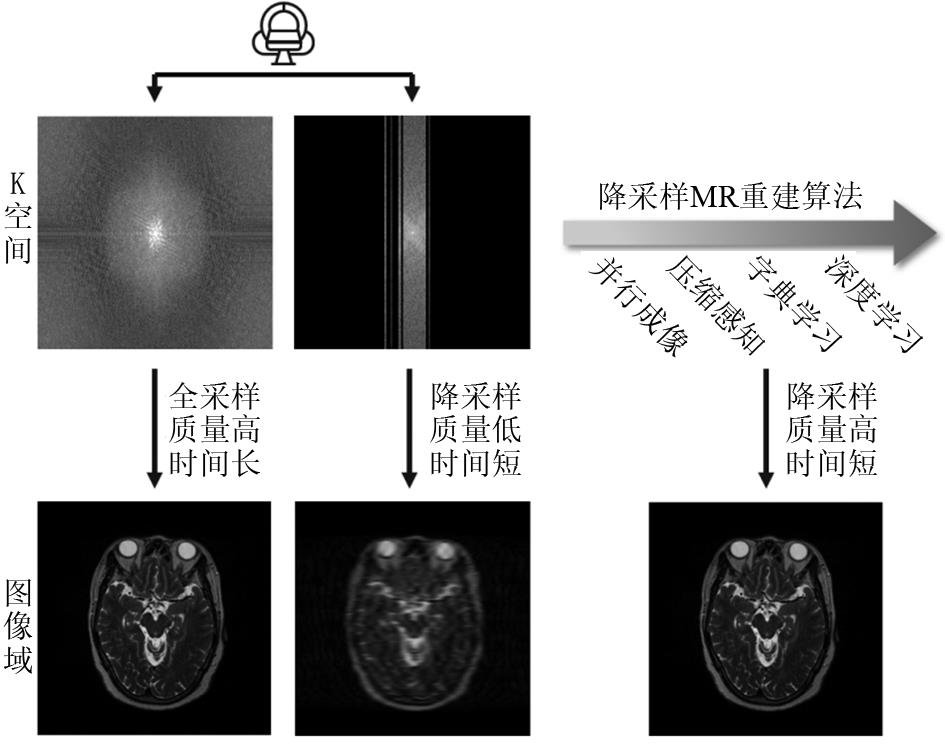

近年来,基于深度学习的方法被提出并成功应用于MR成像,多种针对降采样图像重建的算法相继出现。以大数据作为先验知识,以其更快速的前馈网络处理速度和更好的重建效果,逐渐成为MR重建算法的研究新热点。降采样的MR重建算法经历了半扫描直接重建、基于CS和低秩等方法的传统算法,到基于深度学习的新兴算法(图1),其重建速度逐渐加快,重建效果去伪影、降噪等方面逐渐加强,可适用的降采倍数也逐步提高。以颅脑T2WI为例(图2),在4倍降采样下使用不同类型算法的重建效果,直接重建的图像受到严重的伪影影响,组织结构难以辨认;使用CS的传统算法重建对噪声和伪影有一定的去除作用,但图像质量仍然不佳;使用深度学习算法重建的图像较好地抑制了降采伪影,还原了全采样图像中的解剖结构信息。基于深度学习的MR重建算法将进一步推动医学影像成像速度和质量的提高。